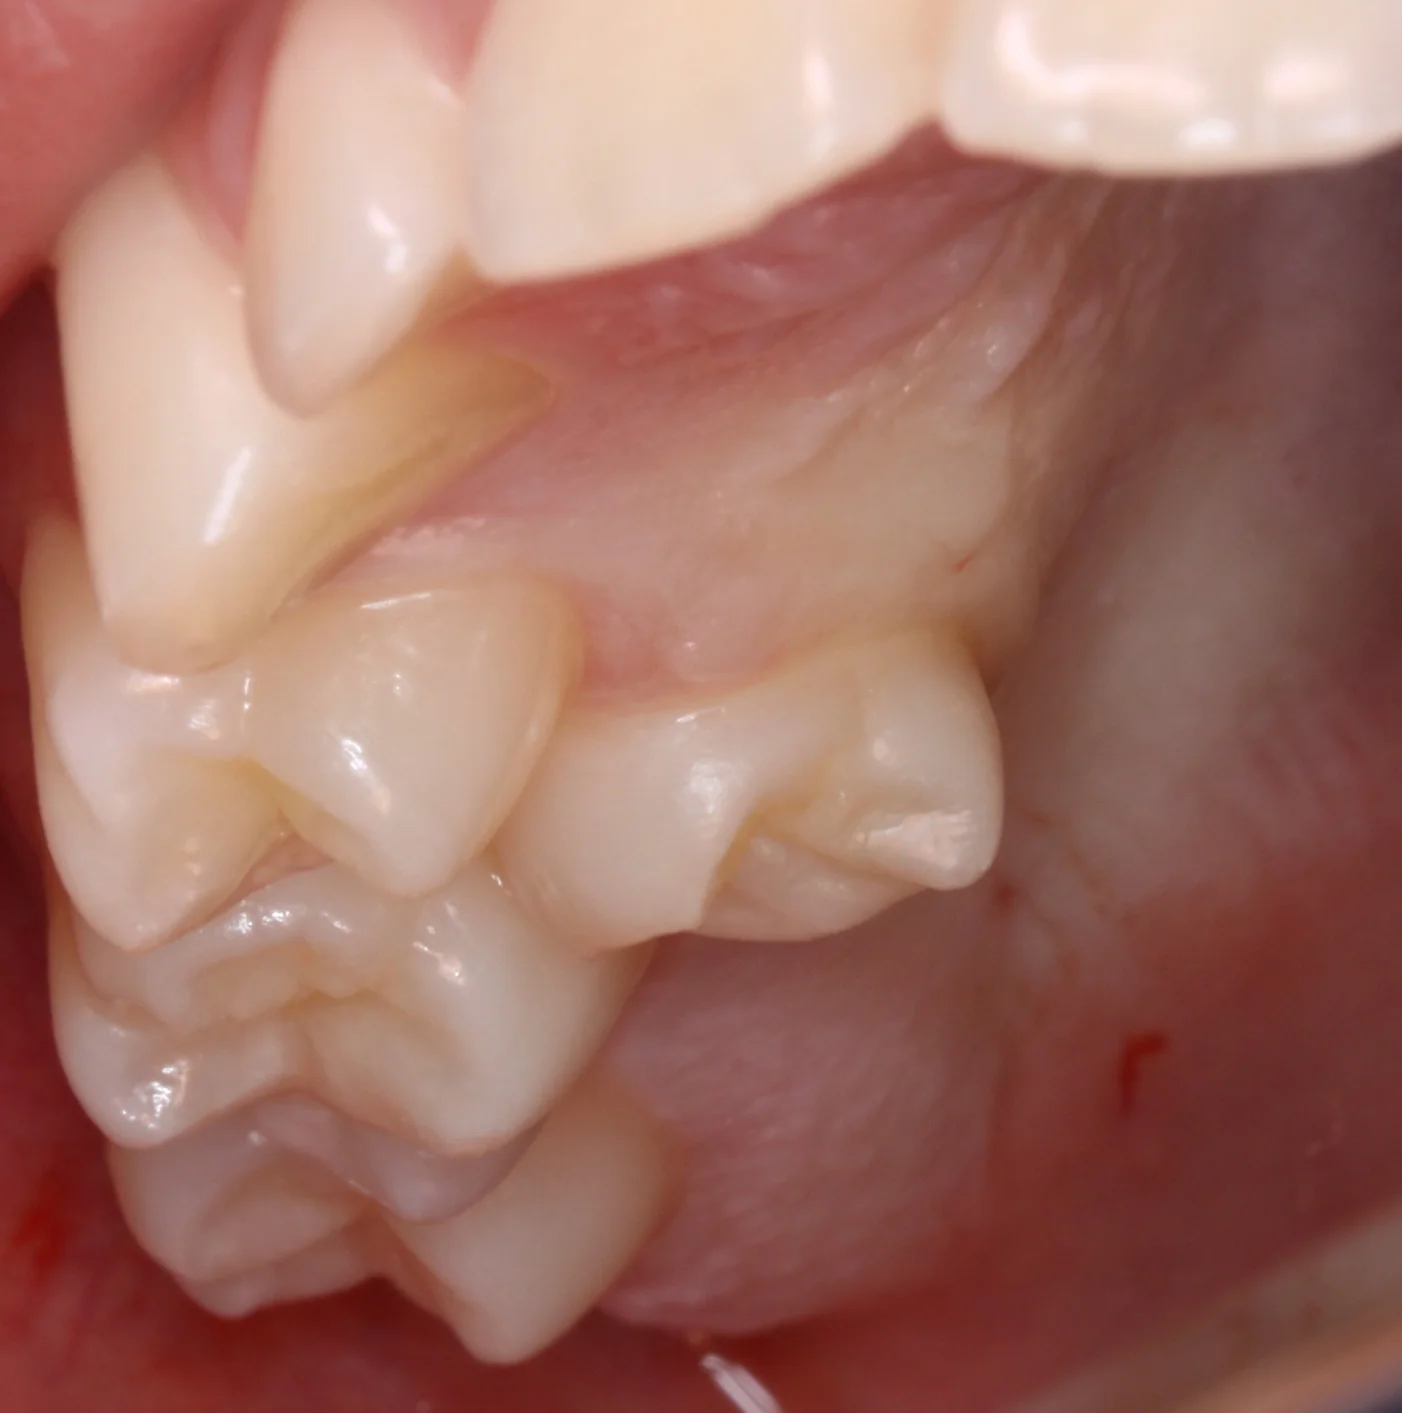

Pige der manglede anlæg for en lille kindtand i undermunden , men havde alt for lidt plads i overmunden til alle sine tænder. Der er foretaget fjernelse af en mælkekindtand og flytning af en lille overkæbekindtand ned på den plads, hvor der mangler en blivende tand. Tanden har på operationstidspunktet kun dannet cirka ¾ af roden. Efter operationen færdigdanner tanden sin rod og vokser op i højde, så den ender det rette sted og kan anvendes til tygning. Tanden vil ofte have en lidt kortere rod end normalt, når den er færdig med at vokse og udvikle sig.